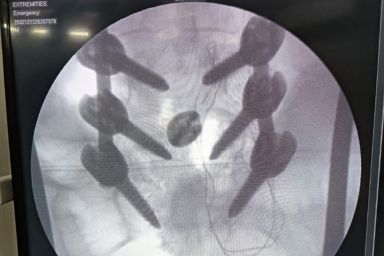

Advanced Orthopaedic Care with Modern OT Facilities by Dr S R Panda

Dr S R Panda is a reputed orthopaedic surgeon in Kolkata offering advanced facilities including General & Joint Replacement OT, Arthroscopy & Trauma OT, and Spine Surgery & Sports Injury OT, ensuring precise diagnosis, modern surgical techniques, and comprehensive bone and joint care under one roof.

Arthroscopy & Trauma OT